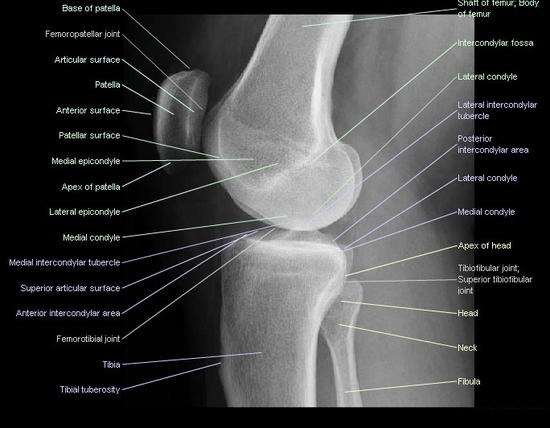

영상평가

- 무릎관절이 잘 열려 보여야 한다.

- 내측 및 외측 대퇴과두(medial/lateral condyle) 가 겹쳐 보여야 한다.